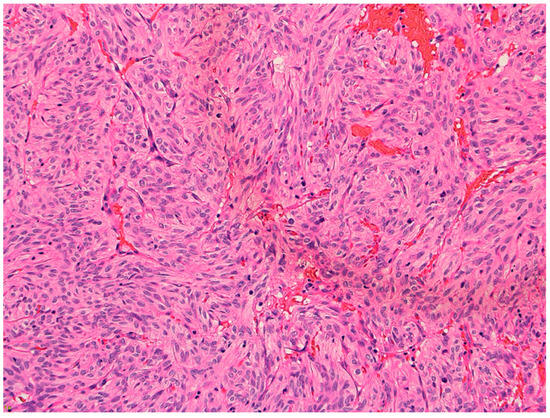

2. Case Presentation